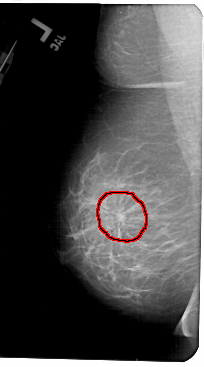

A_1436_1.LEFT_CC

LEFT_CC LINES 5491 PIXELS_PER_LINE 2986 BITS_PER_PIXEL 12 RESOLUTION 43.5 OVERLAY

FILE: A_1436_1.LEFT_CC.OVERLAY

TOTAL_ABNORMALITIES 1

ABNORMALITY 1

LESION_TYPE MASS SHAPE ARCHITECTURAL_DISTORTION MARGINS ILL_DEFINED

ASSESSMENT 4

SUBTLETY 3

PATHOLOGY BENIGN

TOTAL_OUTLINES 1

BOUNDARY